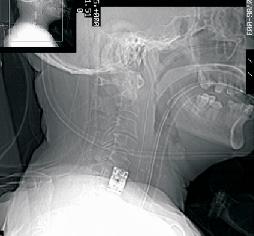

Odantoid Fracture

Facet Dislocation

Tubercular Spondilytis

Cervical Vertebral Fracture

Vertebral Injury

Cervical Cord Compression